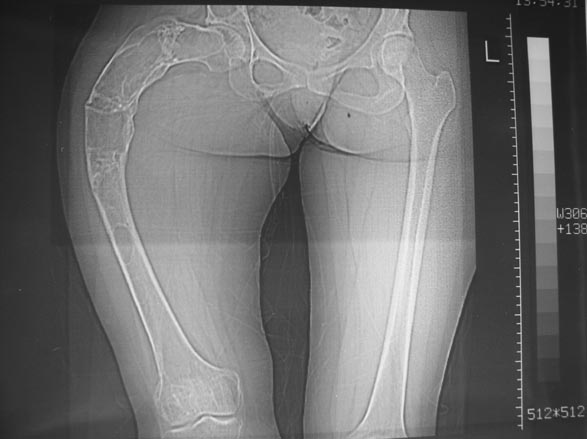

Уважаемые коллеги! С Новым годом и самых светлых пожеланий!В ноябре этого года я обращался с просьбой о помощи в выборе тактики лечения больной с деформацией бедра на почве фиброзной дисплазии. Были получены интересные и очень полезные советы по операции.

Хотелось бы показать, что получилось в результате.Операция выполнялась с помощью А.Н.Челнокова. Очень понравилась технология выполнения блокируемого остеосинтеза с использованием спицевого дистрактора, модифицированный гвоздь с латерализованным проксимальным отделом и возможностью многовинтовой фиксации проксимального и дистального участков бедра.